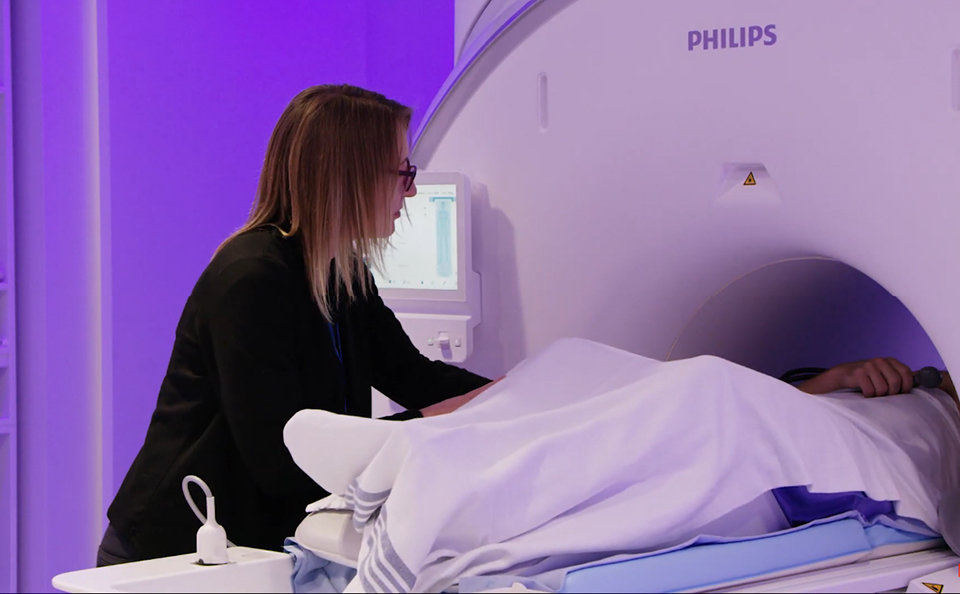

Hear from Laura Barlow, lead technologist at the University of Columbia, how smart features help them contribute to a quick workflow for patient preparation and scanning on their Ingenia Elition 3T system.

Hear Dr. Savatovsky, neuroradiologist at Fondation Rothschild in Paris discuss the benefits that the two Philips Ingenia Elition systems are bringing their clinical practice.